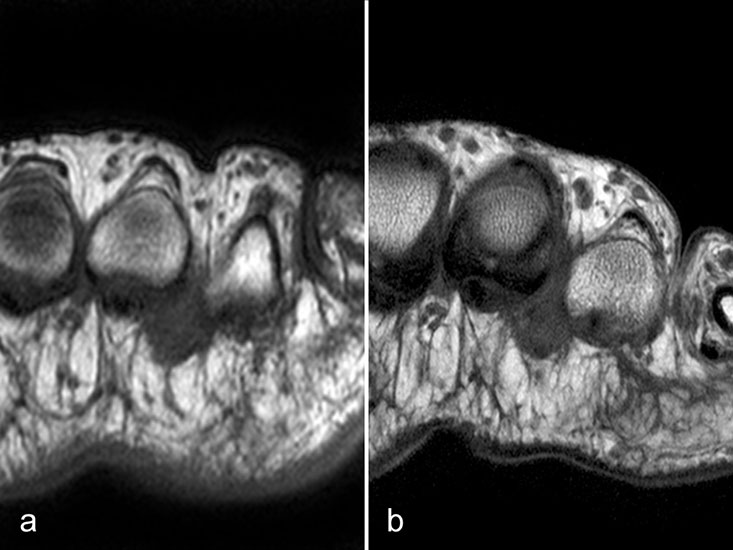

Der Begriff Morton-„Neurom“ ist im Grunde veraltet und irreführend, denn es handelt sich weder um einen Nerven- noch um einen Nervenscheidentumor, sondern um eine perineurale Fibrosierung. Da das interdigitale Gefäßnervenbündel charakteristisch in die Läsion hinein- und distal auch wieder aus der Läsion herauszieht, entsteht lediglich das Bild eines vom Nerven ausgehenden Tumors. Die charakteristischen Merkmale von Morton-„Neuromen“ sind deren Lage plantar auf Höhe der Metatarsaleköpfchen und die oft typische tropfenförmige Konfiguration (Abb. 10).

Aufgrund des hohen Bindegewebsanteils sind sie in der MRT in T2-gewichteten Bildern in der Regel auffallend signalarm, die T1 zeigt eine unspezifische Weichteilintensität. Die Anreicherung nach intravenöser Kontrastmittelgabe ist sehr variabel und erlaubt somit kaum diagnostische Rückschlüsse.

Durch seitliche Kompression des Fußes verlagern sich Morton-„Neurome“ oft weiter nach plantar in die Weichteile. Klinisch entspricht dies dem sogenannten Mulder-Zeichen 4. In der Bildgebung kann man sich den Effekt zu Nutzen machen, indem man in Bauchlage untersucht und durch die seitliche Fixierung eine entsprechende Kompression erzeugt. Die Befunde sind dann oft deutlich besser zu erkennen (Abb. 11).

Morton-„Neurome“ liegen fast immer im zweiten oder dritten Interdigitalraum. Zu beachten ist, dass Morton-„Neurome“ über lange Zeit größenkonstant sein können (Abb. 12) und kleinere Morton-„Neurome“ (unter 5 mm) sehr häufig bei asymptomatischen Gesunden beobachtet werden.